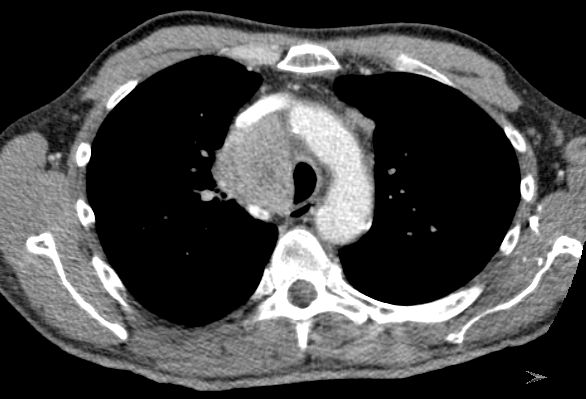

Plattenepithelkarzinom des rechten Lungenoberlappens T3 N2 Mo

NSCLC re OL